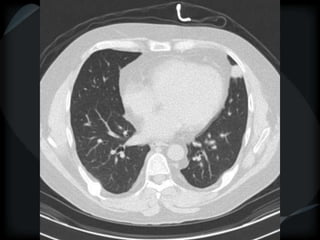

CL + PS emphysema

Pt with more than one form of cyst

CL emphysema + bronchiectasis + honeycomb

smoker with asbestosis

Pt with morethan one form of cyst CL emphysema + bronchiectasis + honeycomb smoker with asbestosis